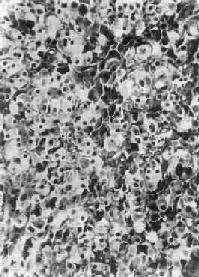

(二)肾上腺皮质癌

肾上腺皮质癌(adrenocortical carcinoma)甚少见,一般为功能性,发现时一般比腺瘤大,重量常超过100g,呈浸润性生长,正常肾上腺组织破坏或被淹没,向外侵犯周围脂肪组织甚至该侧肾。小的腺癌可有包膜。切面棕黄色,常见出血、坏死及囊性变。镜下分化差者异型性高,瘤细胞大小不等,并可见怪形核及多核,核分裂像多见(图15-17)。常转移到腹主动脉淋巴结或血行转移到肺、肝等处。分化高者镜下像腺瘤,如果癌体小又有包膜,很难与腺瘤区别,有人认为直径超过3cm者,应多考虑为高分化腺癌。

图15-17 肾上腺皮质癌